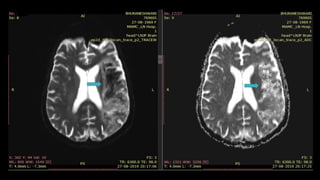

• #121 this are the axial FLAIR and DWI images showing another example of acute lacunar infarct in left hemispheric white matter showing FLAIR AND DWI hyperintensity